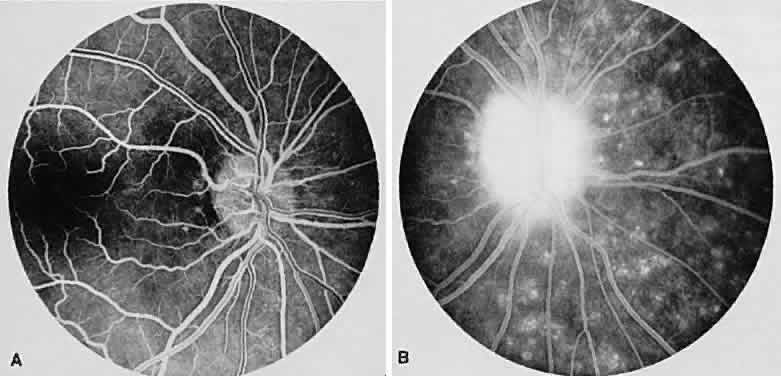

Sympathetic ophthalmia is a rare, bilateral granulomatous, paninflammatory disease that can occur several weeks to years after an ocular injury. Sympathetic ophthalmia is hypothesized to be an autoimmune reaction against a normally sequestered antigen unmasked by an injury. Retinal findings in sympathetic ophthalmia are perivasculitis, papillitis, and yellowish subretinal nodules known as Dalen-Fuchs nodules. Dalen-Fuchs nodules are believed to be transformed retinal pigment epithelium cells or T lymphocytes or both. Areas of choroiditis or granuloma simulating AMPPPE may be seen. Pigmentary disturbance may be noted in the chronic phase of the disease (Fig. 4A and B). Choroidal neovascularization also may develop (see Fig. 4C).

Fig. 4. Sympathetic ophthalmia. A. Areas of pigmentation and small areas of focal atrophy. B. Fluorescein angiogram showing blocked fluorescein corresponding to the areas of pigmentary disturbance with areas of hyperfluorescence representing old areas of inflammation. C. Blocked fluorescence due to subretinal blood in the juxtafovea with associated choroidal neovascularization.

One of two possible fluorescein angiographic findings may be evident. The more common one is identical to Vogt-Koyanagi-Harada syndrome, with early multiple pinpoint retinal pigment epithelial leaks that enlarge with time.11 The second, less common, manifestation is early choroidal hypofluorescence of the Dalen-Fuchs nodules followed by hyperfluorescence in the later phase.12 When exudative retinal detachment occurs, there are confluent areas of subretinal fluorescein pooling.

Two patterns have been identified on ICG angiography.13 The first pattern, observed in a patient with chronic disease, showed hypofluorescent spots in both the intermediate and late phases of the angiogram. The second pattern, reported in a patient with recent onset of the disease, showed hypofluorescent spots in the intermediate phase but faded in the late phase of the angiogram.